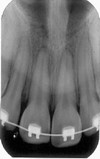

1

Q

A

Anterior Nasal Spine RP

Intermaxillary suture RL

Radiolucent line bordered by parallel radiopaque lines